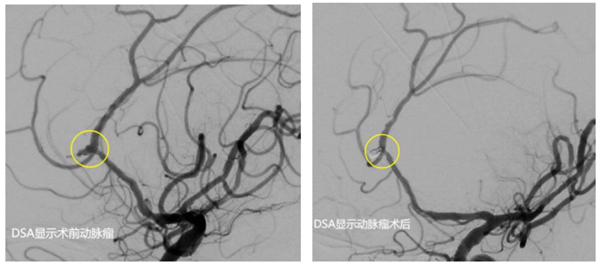

经和家属协商,同意进行手术。该院神经外科介入团队立即启动手术预案。麻醉医师、手术室护士、导管室医护等提前做好术前准备。麻醉成功后,先行脑室钻孔引流,为动脉瘤栓塞争取更多时间。而后,顺利找到了破裂出血的动脉瘤并完美致密填塞,出血情况得到控制。历经4个小时的救治,最终将患者从死亡边缘拉了回来。

颅内动脉瘤并非肿瘤,起病隐匿,缺少特异性,需通过CT/磁共振血管成像、DSA检查方可发现。它是指脑动脉血管由于先天异常或者后天损伤、而导致的血管壁功能减退、弹性下降。其在血压的作用下,逐渐向外扩张膨出、随时有破裂的风险。通俗地说,就是大脑血管鼓出的一个“包”,随着长时间的血流冲击,“包”会逐渐扩大,在薄弱的地方突然破裂,导致患者短时间内会出现剧烈的头痛、意识昏迷、甚至是死亡。颅内动脉瘤的发病率很高,任何年龄均可发病,如果发现不及时,一旦破裂很有可能危及生命安全。一经发现,有手术指征的需尽早手术,即使没有手术指征也需要正规医院随访复查。